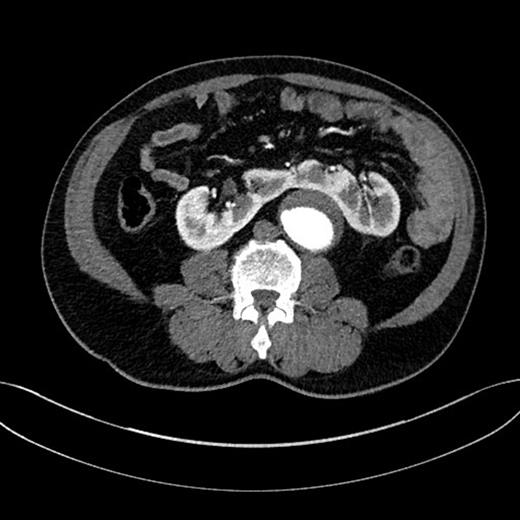

A 67-year-old man, with a known AAA of 4.42 cm, was found to have expansion of the aneurysm diameter to 5.40 cm after undergoing a 3-month surveillance ultrasound scan. The patient's aneurysm was further investigated by a computed tomography angiography (CTA), which demonstrated a 5.50 cm juxtarenal AAA that was not suitable for endovascular AAA repair (EVAR) because of a severely angulated proximal neck. The aneurysm contained a significant amount of mural thrombus. Moreover, the CTA demonstrated a HSK anterior to the abdominal aorta (Fig. 1). Following a multidisciplinary team discussion, an open repair with involvement of both vascular and urology surgeons was decided.